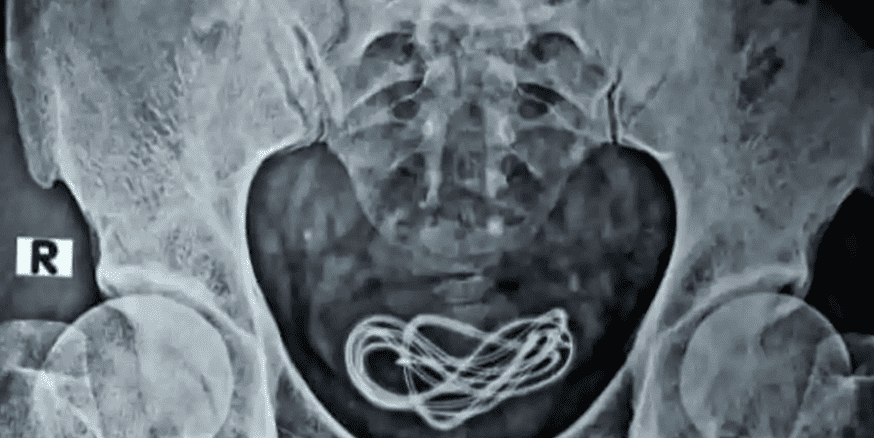

Proses X-Ray dilakukan untuk melihat apakah ada sesuatu di perut. Proses operasi dilakukan tapi mereka tidak menemukan benda yang dicari di saluran pencernaan.

Oleh karena itu, dokter mengambil inisiatif untuk melakukan X-Ray tambahan di ruang operasi dan menemukan bahwa ada sebuah kabel pengisian daya, dan bukan earphone yang sebelumnya diklaim oleh pasien.

Kesimpulan ini diambil karena para dokter telah menemukan kabel pengisian daya bersarang di dalam kandung kemih yang terhubung ke uretra.